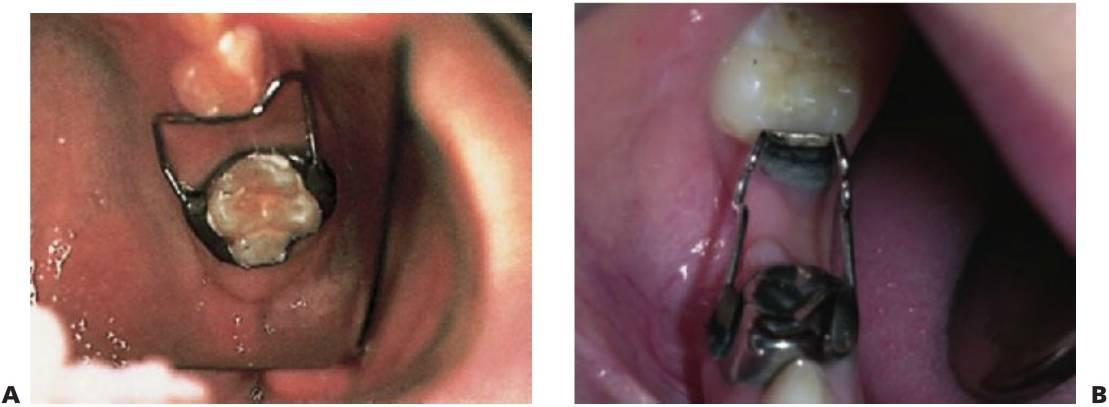

Se debe señalar que la colocación de un aparato fijo en un niño con alto riesgo de caries puede poner en peligro los dientes en los que se ponen las bandas o, incluso, los dientes adyacentes (fig. 11.4).

El aparato de banda y bucle se utiliza de forma general en los casos de pérdida unilateral.

El aparato de Nance o arco lingual se puede utilizar si la pérdida es bilateral.

Los aparatos de zapata distal se pueden utilizar si aún no ha erupcionado el primer molar permanente, pero no se utilizan demasiado debido a los riesgos de infección.